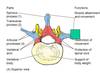

What is the name of the hole that spinal cord is passing through?

Vertebral foramen

What forms neural arch?

Pedicle

Lamina

Body

What is the join between inferior and superior transverse proceeses of vertebra

azygoshypophyseal joint

Name the locations where nerves are exiting from spinal cord

Intravertebral foramen